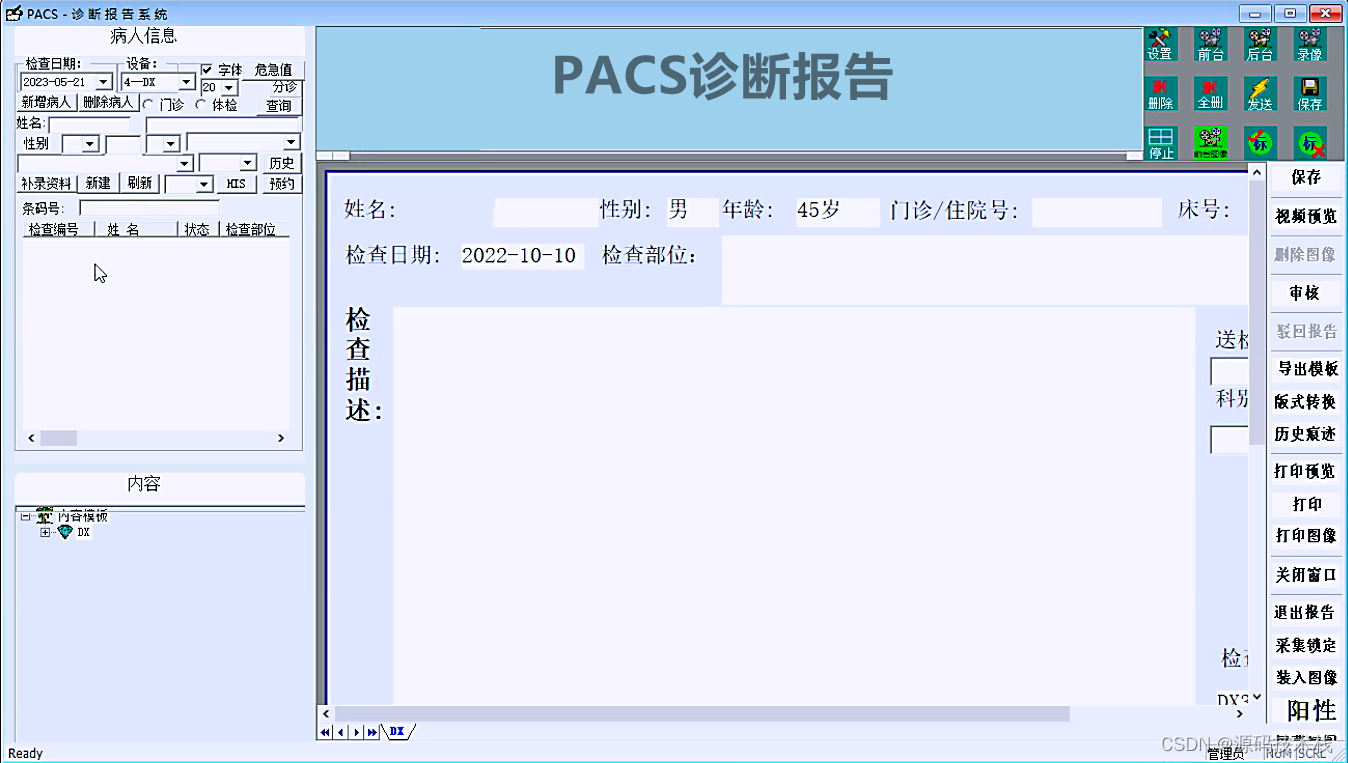

影像报告:PACS可以生成影像报告,将医生的诊断结果和建议以文字形式记录下来,并与相应的影像数据关联起来。这样可以方便医生之间的交流和患者的随访。

RIS:为Radiography InformationSystem的缩写,是放射科信息系统。RIS主要功能和应用包括病人检查预约,影像设备管理与预定,医嘱的输入与管理,病人与设备预约的管理,影像诊断报告和生成与管理,划价,收费。

功能包括:预约分诊、排队叫号、放射/医技科室信息管理系统、影像处理、医技报告书写、WEB图像浏览(院内)、影像报告发放/共享。